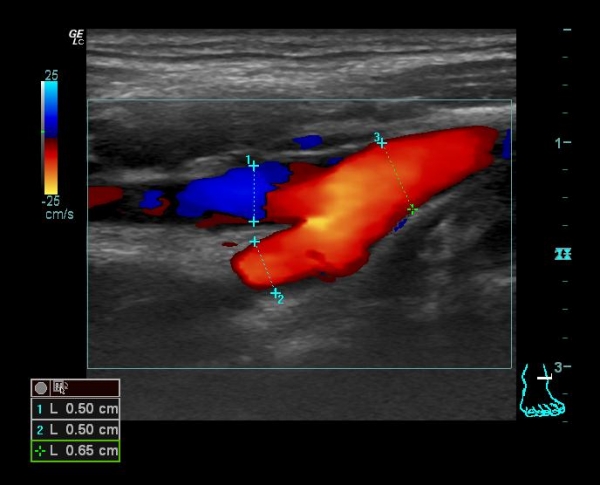

Случай №1 (женщина)

Из картинок видно, что соотношение ВСА/НСА у мужчин ближе к 1, у женщин >1

То есть относительно притока к головному мозгу, у женщин возможности выше, чем у мужчин. Отсюда выводы? (вопрос 3). Подумаем. Потом обсудим, как интерпретирует Оксфорд.